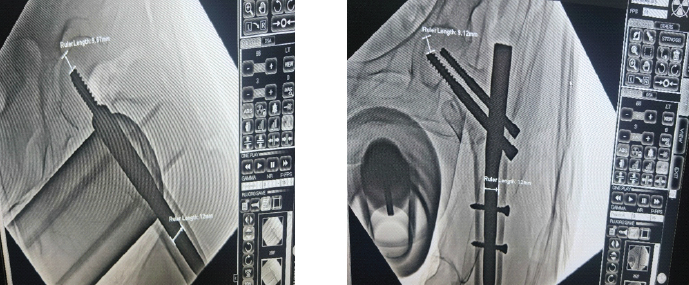

The TAD, introduced by Baumgaertner et al.[13]. It is widely regarded as the gold standard for predicting the risk of lag screw cut-out. This metric applies to the positioning of both intramedullary nails and sliding hip screws.

In this study, TAD was measured specifically in relation to the lag screw, excluding the derotation screw, with adjustments made to account for radiographic magnification [14], using the software available in the C-ARM fluoroscope and calibrating measurements with the known size of the PFN nail introduced in the fracture. TAD is calculated as the sum of two distances: The distance from the tip of the lag screw to the apex of the femoral head measured on the AP view (XAP) and the corresponding distance measured on the lateral view (XLat). Both measurements are corrected for magnification using the true diameter of the lag screw (Dt11rue) as a reference, i.e, TAD = XAP + XLat.

(Fig. 4)

Figure 4: Tip apex distance in anteroposterior and lateral views.